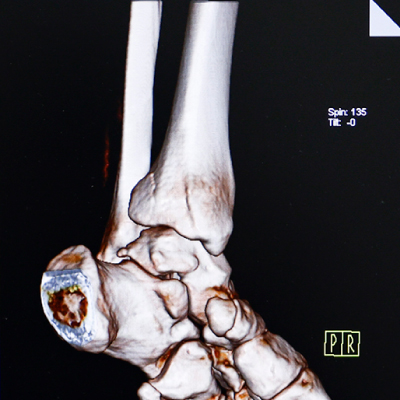

Ⅹ線CT装置(16列マルチスライス) Siemens SOMATOM Scope

X線投影データをもとに、コンピューターによって再構成された画像により体内の形態情報を得ることができます。

細かいスライスデータにより、目的部位の三次元画像や任意の断面の画像を作成し、正確な診断に寄与する画像データを得ることができます。

使用するX線量は最適化され、被ばくの低減に努めています。

予約不要。即日検査いたします。(単純CTのみ)

医師の診断~CT撮影まで、受診日当日に即日検査いたします。

ご希望の方は栗東診療所を受診のうえ、医師にご相談ください。